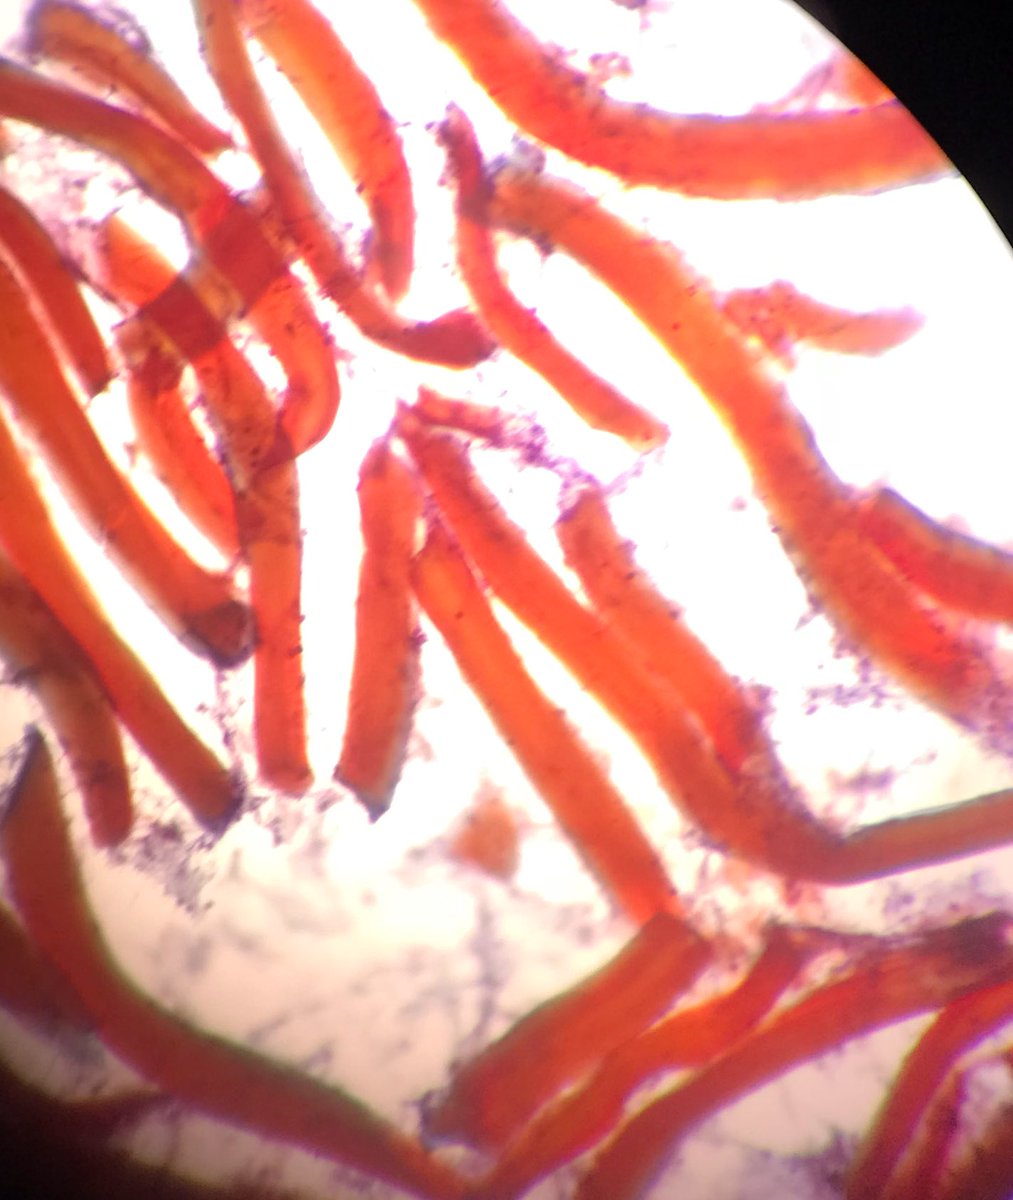

Hellow #pulmonarypath this FNA is from left lung lesion 22 y male history of trauma? There are many foreign material fragments, inflammation, histiocytes and the microorganism below. Any idea what are they ? @yro854 @smlungpathguy

There are many foreign material fragments, inflammation, histiocytes and the microorganism below. Any idea what are they ? @yro854 @smlungpathguy